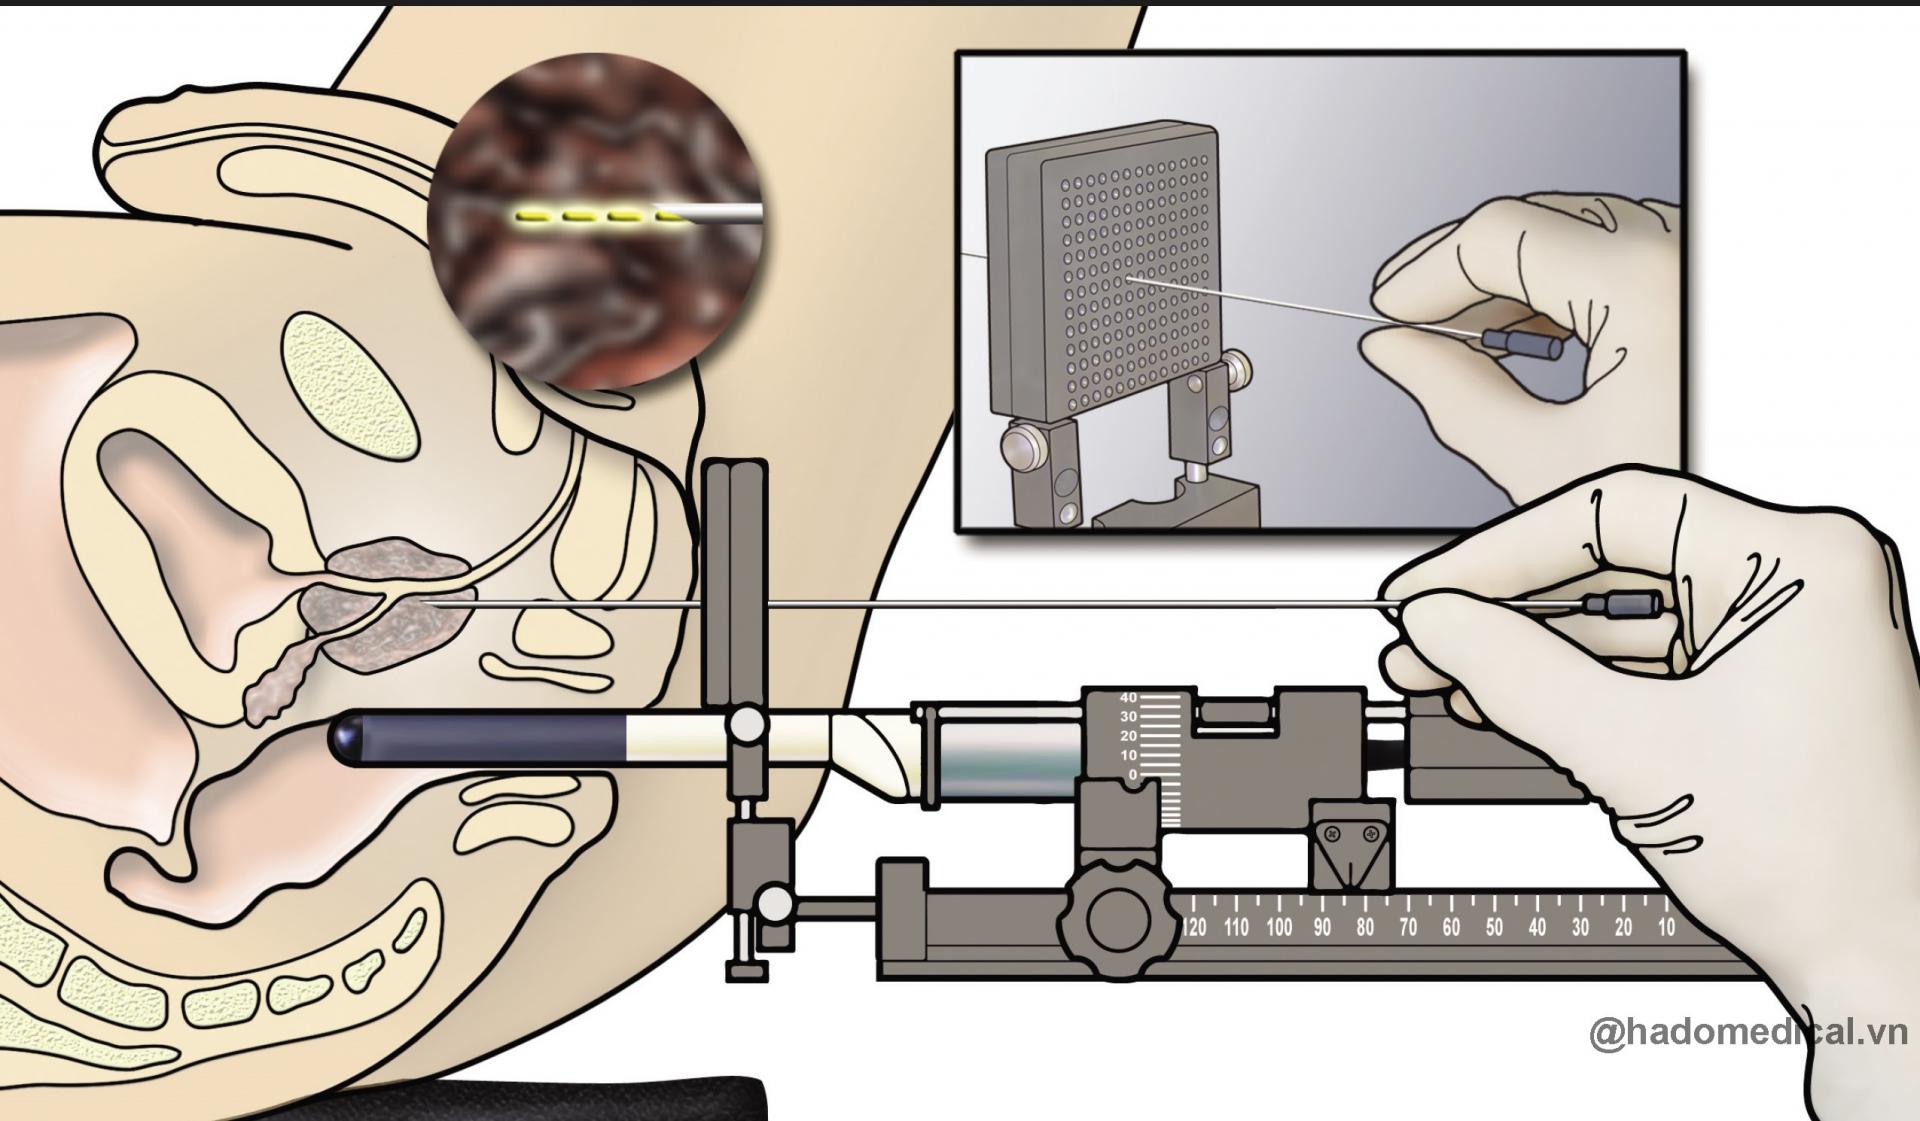

Gá sinh thiết và điều trị U xơ Tiền liệt tuyến đặt hạt phóng xạ

- Modul sinh thiết và điều trị u xơ tiền liệt tuyến (TUR) qua ngả trực tràng dưới dướng dẫn siêu âm _Prostate Imaging & Biopsy: Đặc biệt kỹ thuật điều trị u xơ tiền liệt tuyến bằng hạt phóng xạ (brachytherapy)

- Gá sinh thiết dùng với đầu dò siêu âm các loại